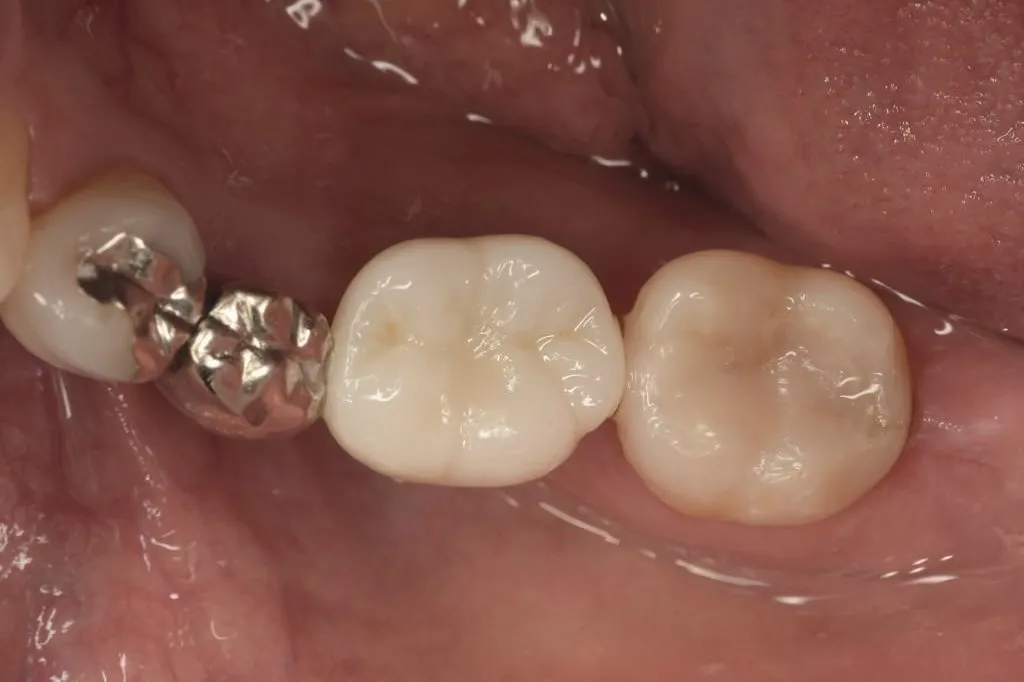

インプラント治療症例①

インプラント治療症例②

インプラント治療症例③

インプラント治療症例④

インプラント治療症例⑤

インプラント治療症例⑥

歯周病などで骨が少なくなった患者さんに対して行う、骨を再生させる処置(ソケットプリザベーション)